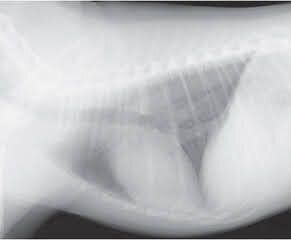

犬の心臓のレントゲン画像

参考・写真/「いぬのきもち」2018年7月号『3号連続企画 犬の死因トップ3を学ぼう!知っておきたい犬の「心臓病」』

• 内科治療では心不全のコントロールがうまくできず、重篤な状態。

• 早めの手術が望ましいが、一方で手術の死亡率は高い。